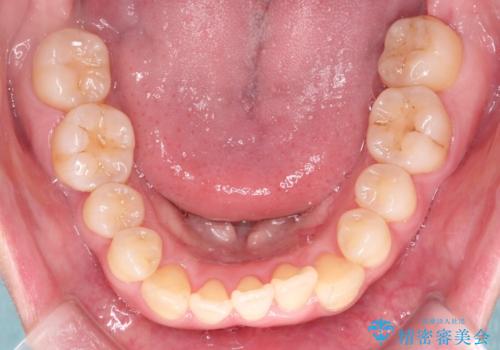

- 前歯の噛み合わせが悪いことを主訴に来院されました。

歯周病も併発していたため、歯牙への負担が少なくなるように治療計画をたて、インビザラインにて治療を完了しました。

矯正開始前に半年間、歯周治療を行ってからインビザラインを装着しています。